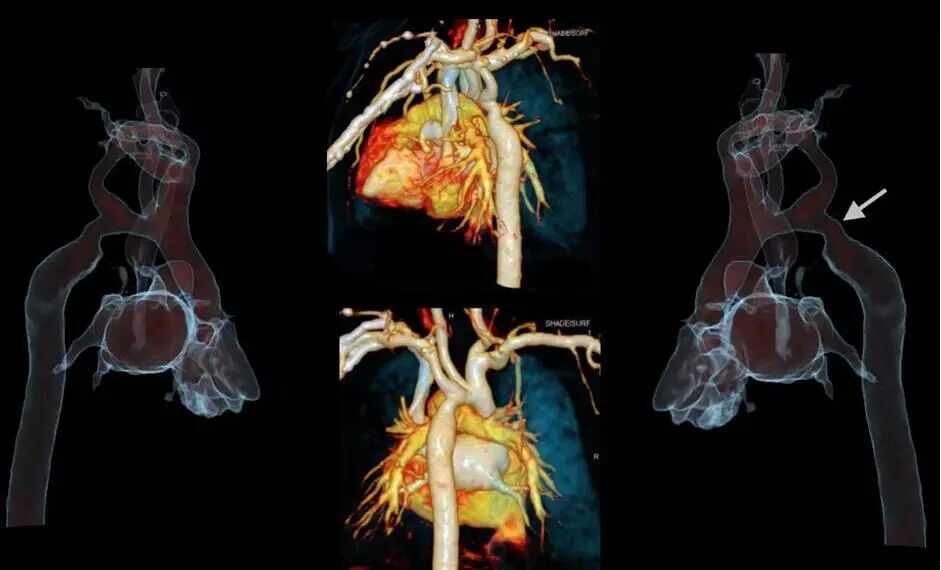

Force CT轉(zhuǎn)速可達0.25s/圈,雙套球管及探測器交叉90度設(shè)計,相當于單源CT 0.125秒每圈,心臟成像時間分辨率66ms,真正跨越自由心跳門檻100ms,因此可以做到自由心率的心臟冠脈CTA等檢查。

西門子獨創(chuàng)的Turbo Flash模式,掃描速度達每秒73.7cm/s,可在1秒內(nèi)完成胸腹大血管、頭頸心一站式篩查,對胸痛三聯(lián)征、心腦聯(lián)合成像、頭胸心腹部及全程主動脈等多部位一站式聯(lián)合掃描等檢查都能很好的完成。

4.擺脫心電門控的心臟掃描:

SOMATOMForce實現(xiàn)了前所未有的0.25秒/圈的轉(zhuǎn)速,0.066秒的心臟成像快門時間,憑借史上最快的737mm/s掃描速度,全面突破血流、呼吸、心跳的束縛,全面“凍結(jié)”人體生理運動,甚至可以擺脫心電門控的束縛,實現(xiàn)自由無“線”心臟CT掃描。

△66ms單扇區(qū)時間分辨率,任意心率、節(jié)律高清成像

5.1秒一站式多血管同時掃描:

SOMATOMForce 開源CT的73.7厘米/秒的業(yè)內(nèi)最快掃描速度,已突破血流方向相反的成像難題,使得CTA聯(lián)合掃描在血管成像領(lǐng)域應(yīng)用研究將更加深入,未來低輻射和低對比劑量一站式多部位多血管CTA(頭頸冠脈成像、胸痛三聯(lián)征、心臟+腹部血管+下肢血管成像)將成為指導(dǎo)心臟和外周血管性疾病介入診療的重要工具。